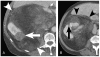

Materials and methods: We identified CT scans of 20 patients (13 women and 7 men; mean age, 63 years) with either perirenal liposarcoma (n = 11) proven at histopathology or large exophytic angiomyolipomas (n = 9) determined by 2-year stability (n = 6) or histopathology (n = 3). Two independent readers unaware of the final diagnoses recorded the presence of the following CT findings: (1) tumoral vessel extending into the renal cortex, (2) tumoral vessel extending into the renal hilum, (3) renal parenchymal defect at the site of tumor contact, (4) intratumoral hemorrhage, (5) nonfat attenuating intratumoral nodules, and (6) calcification.

Results: A tumoral vessel extending into the renal cortex was seen only in angiomyolipomas (7 and 6 of 9 patients versus 0 and 0 of 11 liposarcomas for readers 1 and 2, respectively; P < 0.005 for both). A parenchymal defect was more commonly seen in angiomyolipomas (7 and 6 of 9 angiomyolipomas versus 1 and 1 of 11 liposarcomas for readers 1 and 2, respectively; P < 0.05 for both). Calcifications were seen by both readers in 6 of 11 liposarcomas but not in any angiomyolipomas (P < 0.05). The other recorded findings were not useful in distinguishing CT features (P > 0.1 for both readers).

Conclusions: In the evaluation of a fatty perinephric mass at CT, the presence of a tumoral vessel extending into the renal cortex or a renal parenchymal defect at the site of tumor contact strongly favors the diagnosis of exophytic angiomyolipoma, whereas calcifications suggest liposarcoma.